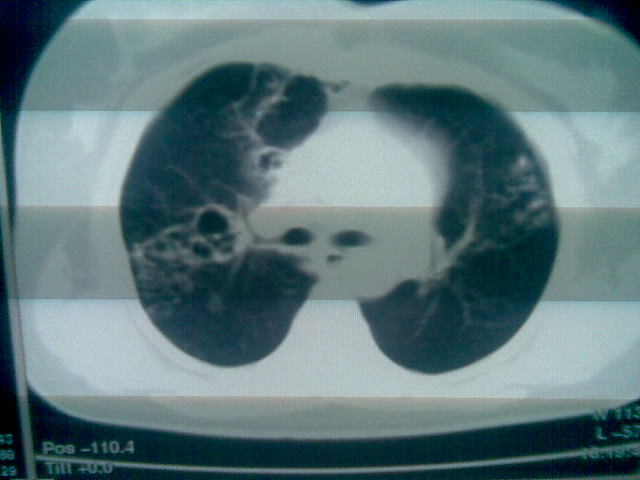

标题: CT24013:女,46岁,主诉既往有慢性咳嗽咳痰病史!近几天间 [打印本页]

标题: CT24013:女,46岁,主诉既往有慢性咳嗽咳痰病史!近几天间

两上肺均见有斑片条结及蜂窝状环状低密度影,以右侧居多,考虑肺结核并支扩可能。

支扩并感染,结核不能排除,建议结合实验室检查或痰检。